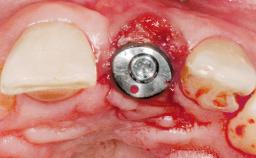

| # of Implants | 1 |

| Type of Implants | One-Piece |

| Attachment | One-Piece |

| Placement Protocol | Immediate implant placement |

| Tooth Site | Maxillary incisor or canine |